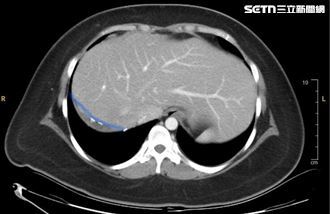

▲陳姓醫大生遭洗車工酒駕撞死,檢方相驗近一步電腦斷層查死因。(圖/翻攝畫面)

家屬南下台中認屍悲痛欲絕,質疑「為何台中酒駕這麼多?」,依照法律將由國民法庭審判,檢察官有舉證責任,釐清詳細死因後,屆時才能作為呈堂證供。中檢8日相驗後決定進一步安排電腦斷層掃描,釐清確切死因。家屬至於照完電腦斷層掃描的結果,可能要等待一禮拜才能出爐,醫大生的母親難過痛哭表示:「難道我的孩子頭七要在台中?」,

中檢也說明,電腦斷層掃描(CT)之進行掃描、影像判讀、完成書面報告整體 流程需要一定時間,實務上多於7日內完成。但避免讓家屬南北奔波勞累,預計盡速處理,醫大生一定能在頭七前「回家」。